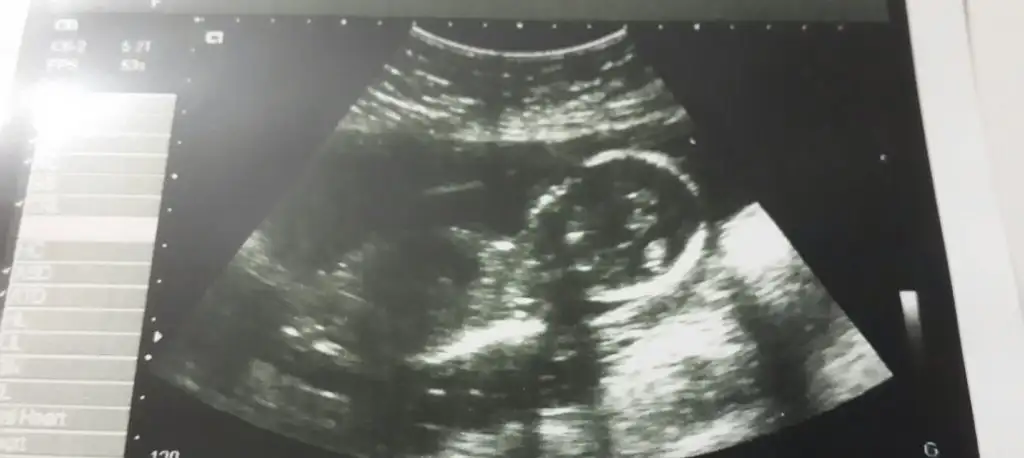

Kızlar selammmmmmaşallah kuzucukları ultrason fotoları koyulmus benim 10 gun oncenin görüntüsü var hiç aklıma gelmemişti koymak sizden görüp koycammm ben de Eki Görüntüle 1371545